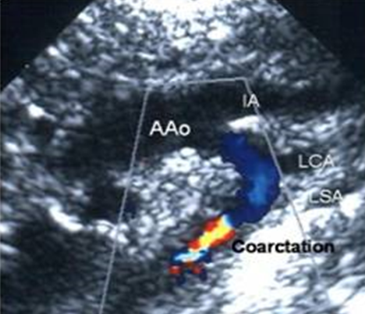

bicuspid AO valve is associated with

dilatation of aortic sinuses and ascending aorta

coarctation of aorta

aneurysm

aortic dissection

what is bicuspid ao valve associated with

dilatation of ao

coarctation

ao dissection